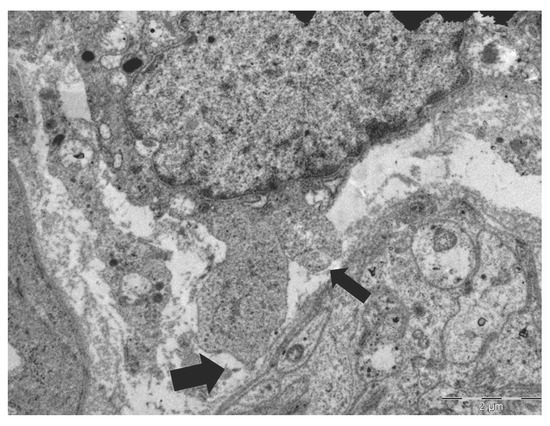

Background: Perineural invasion (PNI) is a recognized pathway for cancer spread and is associated with poor outcomes in gastric cancer. However, the initial morphological characteristics of tumor–nerve interactions in early gastric cancer, particularly at the ultrastructural level, remain insufficiently defined. Case Presentation: We report a case of a 49-year-old man diagnosed with type IIc early gastric cancer. Histological examination revealed a combined poorly cohesive carcinoma (PCC)-NOS/signet-ring cell (SRC) histotype. Tumor invasion reached the middle third of the submucosa and was accompanied by a mature desmoplastic reaction, with metastases identified in two perigastric lymph nodes (pT1bN1M0). Transmission electron microscopy (TEM) revealed unmyelinated nerve fibers embedded within the submucosal desmoplastic stroma, in close proximity to infiltrating neoplastic cells. Several tumor cells exhibited cytoplasmic projections ranging from single extensions to multiple prominent pseudopods, resulting in an amoeboid morphology. Notably, an unmyelinated nerve process was observed within a cytoplasmic invagination of an individual tumor cell. Conclusions: Taken together, these ultrastructural findings provide novel and previously undescribed morphological evidence of a specific interaction between amoeboid tumor cells and peripheral unmyelinated nerve fibers within the submucosal desmoplastic stroma of early gastric cancer. The biological and clinical significance of this interaction in the early stages of perineural invasion warrants further investigation. Full article

Show Figures

Figure 1